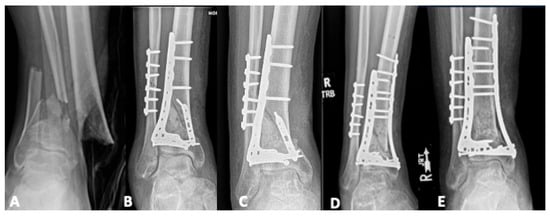

Radiological Landmarks for Joint Line Level in Challenging Total Ankle Arthroplasty

Background: Although Total Ankle Arthroplasty (TAA) is primarily performed for post-traumatic ankle arthritis with joint disruption, anatomical landmarks for Joint Line (JL) level are typically preserved. However, severe Post-Traumatic Bone Loss (PTBL) or TAA revision may render some landmarks unidentifiable, challenging JL restoration. [...] Read more.

Background: Although Total Ankle Arthroplasty (TAA) is primarily performed for post-traumatic ankle arthritis with joint disruption, anatomical landmarks for Joint Line (JL) level are typically preserved. However, severe Post-Traumatic Bone Loss (PTBL) or TAA revision may render some landmarks unidentifiable, challenging JL restoration. Methods: Patients undergoing customized TAA for severe PTBL or revision were enrolled. Custom-made implants, based on 3D CT scans, were designed to address bone defects and provide adequate bone support. Evaluated parameters, measured on bilateral ankle weight-bearing radiographs taken preoperatively and 6–8 months postoperatively, included JL Height Ratio (JLHR) and the distances from JL to the Lateral Malleolus apex (LM-JL), the posterior colliculus of the Medial Malleolus (MM-JL), and the Gissane Calcaneal Sulcus (CS-JL). Reproducibility and variability were assessed, and comparisons were made between radiological parameters measured at TAA and those at the contralateral ankle. Results: Thirteen patients were included. Intra- and interobserver reliability demonstrated excellent values. The least variability was observed in the LM-JL distance. Statistically significant correlations were found between CS-JL and MM-JL distances in the operated limb and between the CS-JL of the operated limb and the contralateral ankle. While TAA parameters did not show statistically significant differences compared with the contralateral ankle, a trend toward proximalization of the JL was noted. Conclusions: This study demonstrated good reproducibility of the analyzed parameters for evaluating JL in TAA among patients with severe PTBL or undergoing revision surgery. However, these parameters cannot be deemed fully reliable. Given their potential weaknesses, it is crucial to identify more reproducible values, preferably ratios. Full article

Show Figures

Figure 1